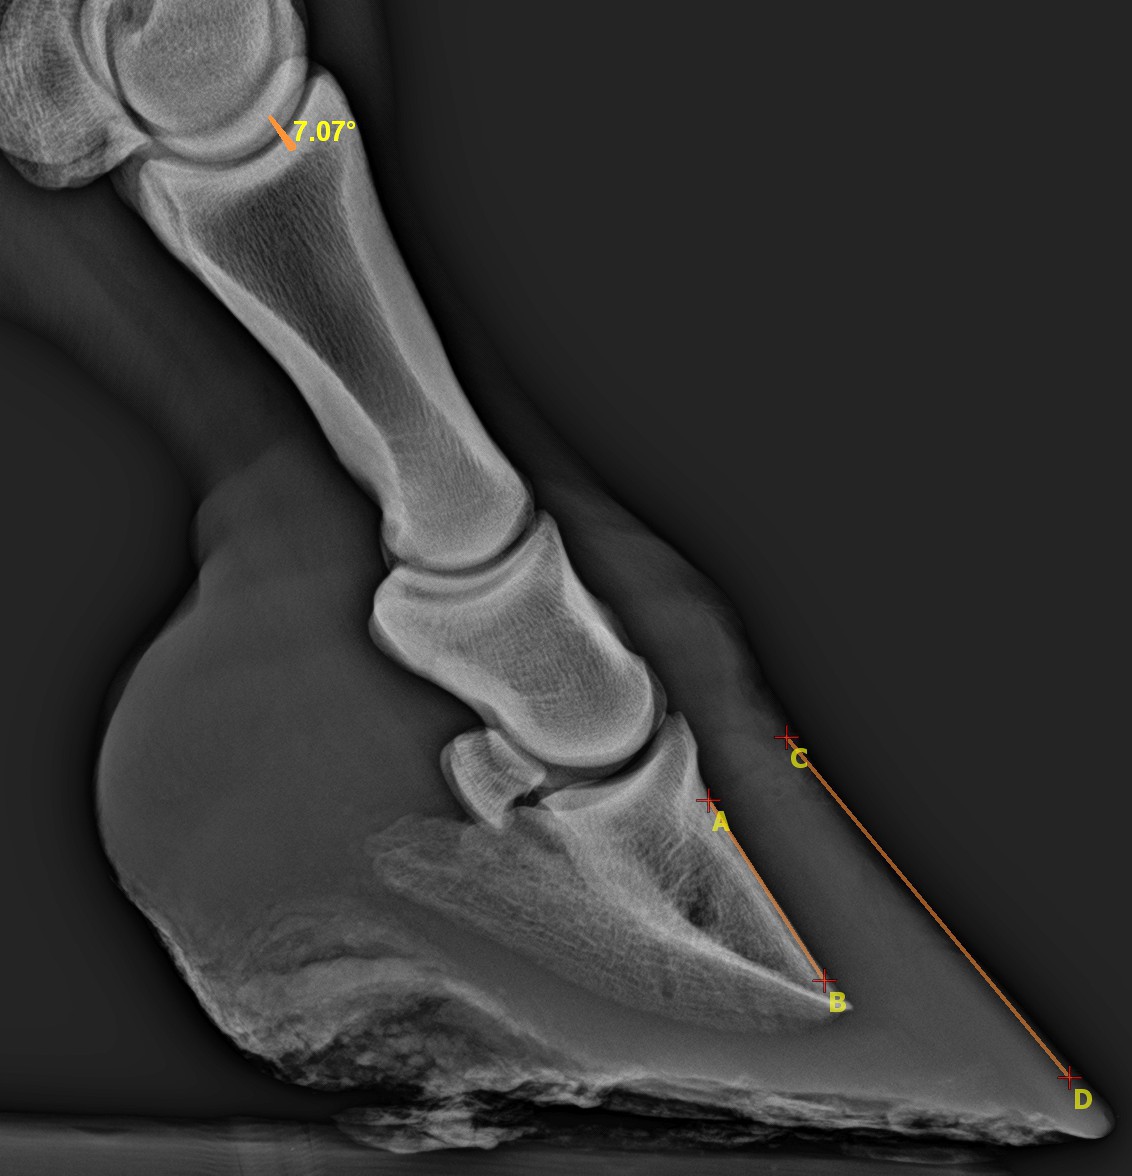

7 fokos rotáció látható, ami az irha gyulladása miatt fellazuló összekötttetés miatt jön létre. A patacsont és a szaru nem párhuzamos, mint egészséges lovak esetében.